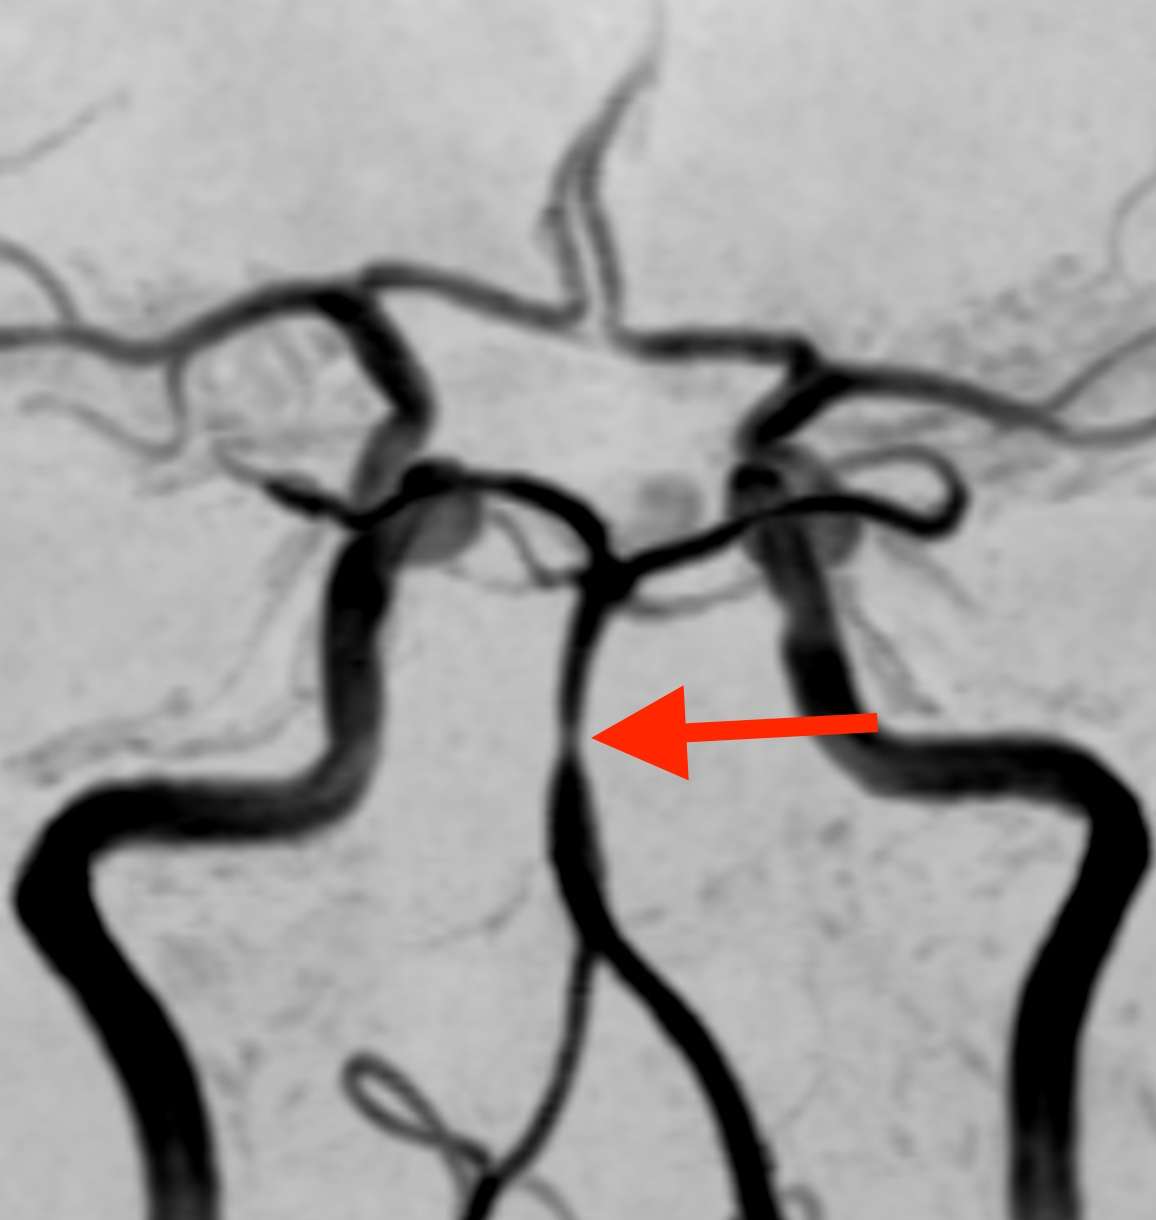

MRI検査で脳の血管を見たところ、

脳底動脈という血管の一部がくびれて細くなっており、その下の部分では、血管がソーセージのような形に膨らんでいます。そこで、この所見から可逆性脳血管攣縮症候群(RCVS)と診断しました。